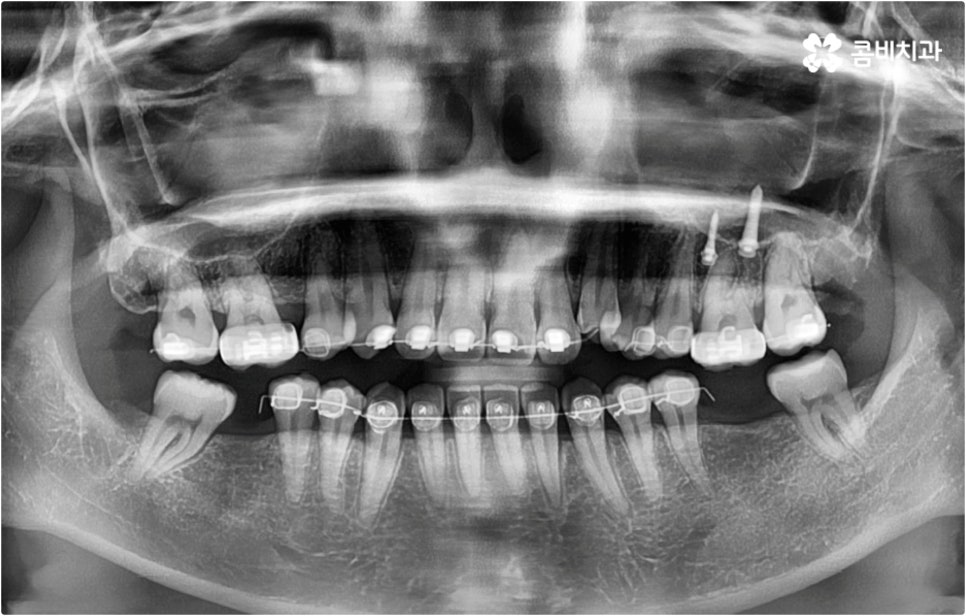

이런 때는 치아설측교정 대신 비교적 잘 보이는 윗니는 설측으로 진행하고, 입술에 가려 잘 보이지 않는 아랫니는 순측(입술쪽)으로 진행하는 콤비교정을 이용하면 발음, 이물감, 통증 문제를 해결할 수 있습니다. 콤비교정 시 치아 겉면에 부착하는 아랫니 브라켓의 경우 치아와 색상이 비슷한 세라믹 재질을 이용하기 때문에 심미성도 크게 떨어지지 않으며 치아설측교정 으로 전체를 진행하는 것 보다 비용적인 부담도 줄여주므로 설측 교정 치료를 생각하시는 분들이라면 콤비교정 역시 함께 알아보시길 권유드리고 있어요.

이와 같이 치아설측교정 과 콤비교정은 브라켓을 치아 안쪽으로 붙여서 치료하는 방식이기 때문에 굉장히 고난도의 복잡한 교정 치료라고 할 수 있습니다. 교정에 대한 높은 이해도와 해부학적으로 뛰어난 노하우, 풍부한 경험을 통해 축적한 세심한 기술력을 갖추고 있는 의료진에게 치료를 맡기는 것이 중요하며 정밀 디지털 검진 장비를 통한 정확한 검사 결과를 바탕으로 무리하지 않게 진행하실 필요가 있어요. 또한 양치질을 할 때 음식물 제거가 쉽지 않으므로 환자분들 본인이 평상시 신경써서 닦아주시는 것은 물론 꼼꼼한 케어시스템을 통해 주기적으로 관리해 주는 치과에서 교정 치료 및 사후 유지 관리까지 철저하게 받아보시길 권유드리고 있습니다.